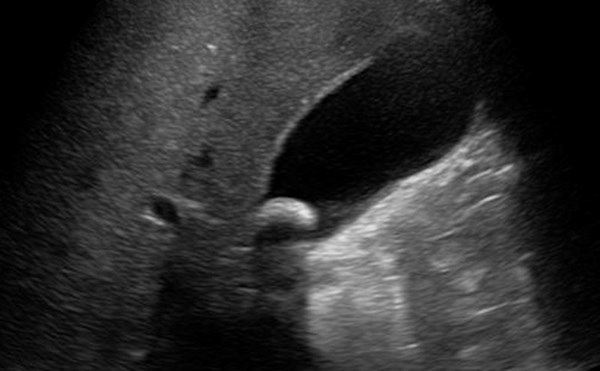

Early Pregnancy